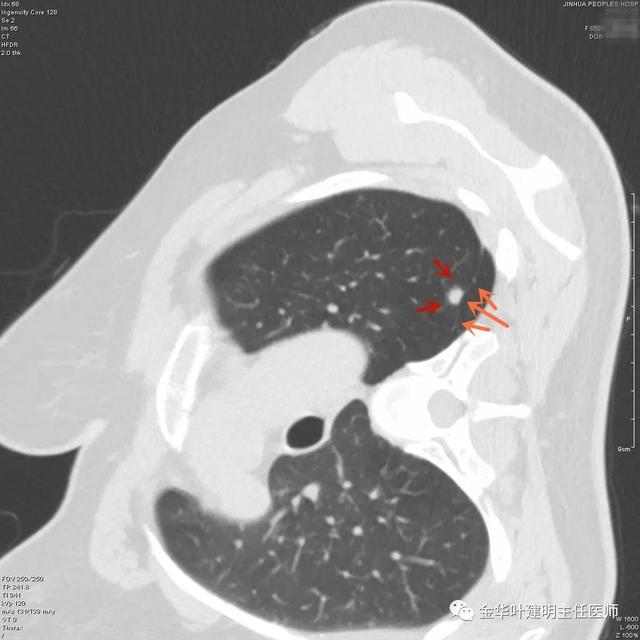

上图是纤维增生,但我们看病灶有明显的叶间胸膜牵拉,虽然力度弱,但这么小的病灶能指望它有多少力度呢?恶性还是不能除外的。